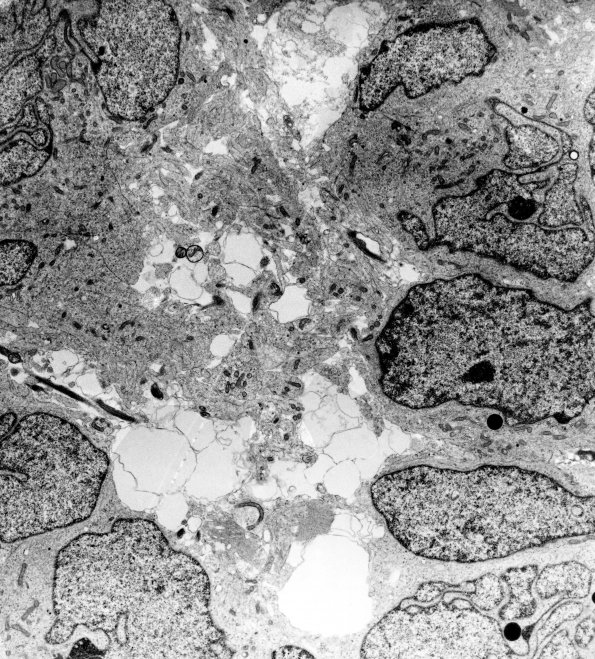

13C2 Medulloblastoma (Case 13C) EM 1 - Copy

Primitive cells surround neuroblastic processes.